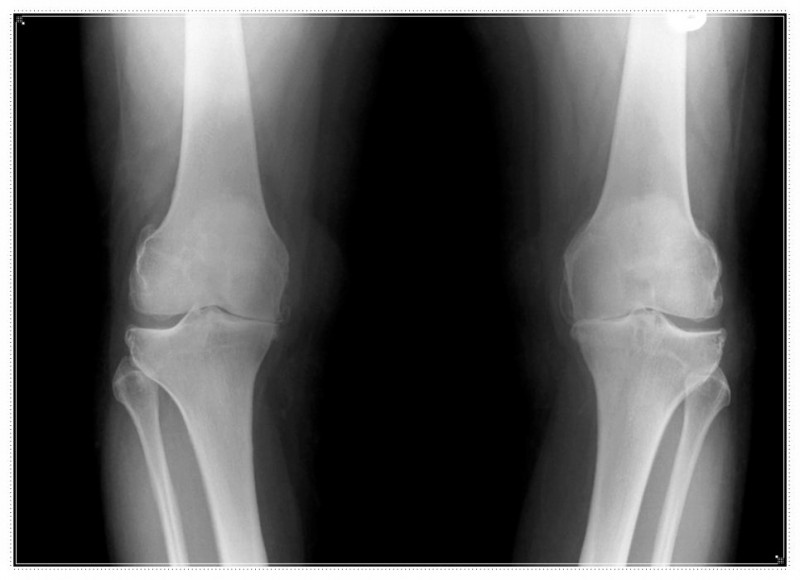

무릎의 불편함을 겪는 분들 중에는 휜다리, 평발, 혹은 무릎이 뒤로 과하게 꺾이는 반장슬과 같은 구조적인 문제를 이미 가지고 계신 경우도 적지 않습니다.

- 오래 서 있을 때 무릎 안쪽이 특히 더 아프거나, 신발 굽이 한쪽만 유독 빨리 닳지는 않으신가요?

- 혹은 똑바로 섰을 때 양 무릎 사이가 유난히 멀어 보이지는 않으신가요?

이러한 증상은 신체 정렬의 불균형을 알리는 구조 요청일 수 있습니다.